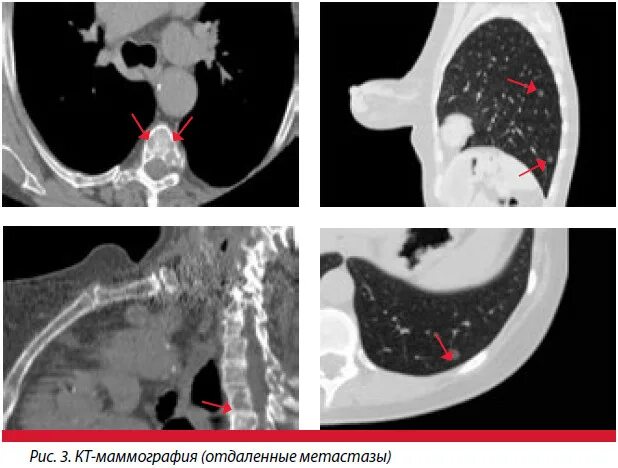

Форум после кт